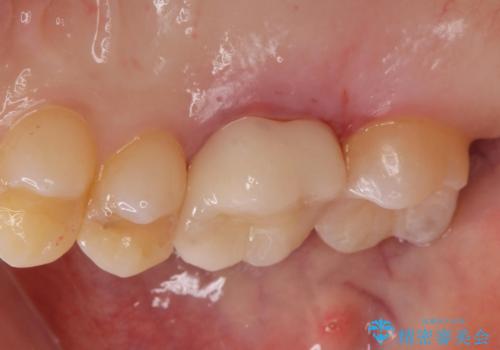

一番奥の歯は古い樹脂の治療の後がありましたのでセラミックの詰め物で治療しました。

適合の良いクラウン、詰め物が入りました。

適合が良いことで虫歯の再発のリスクが低くなります。